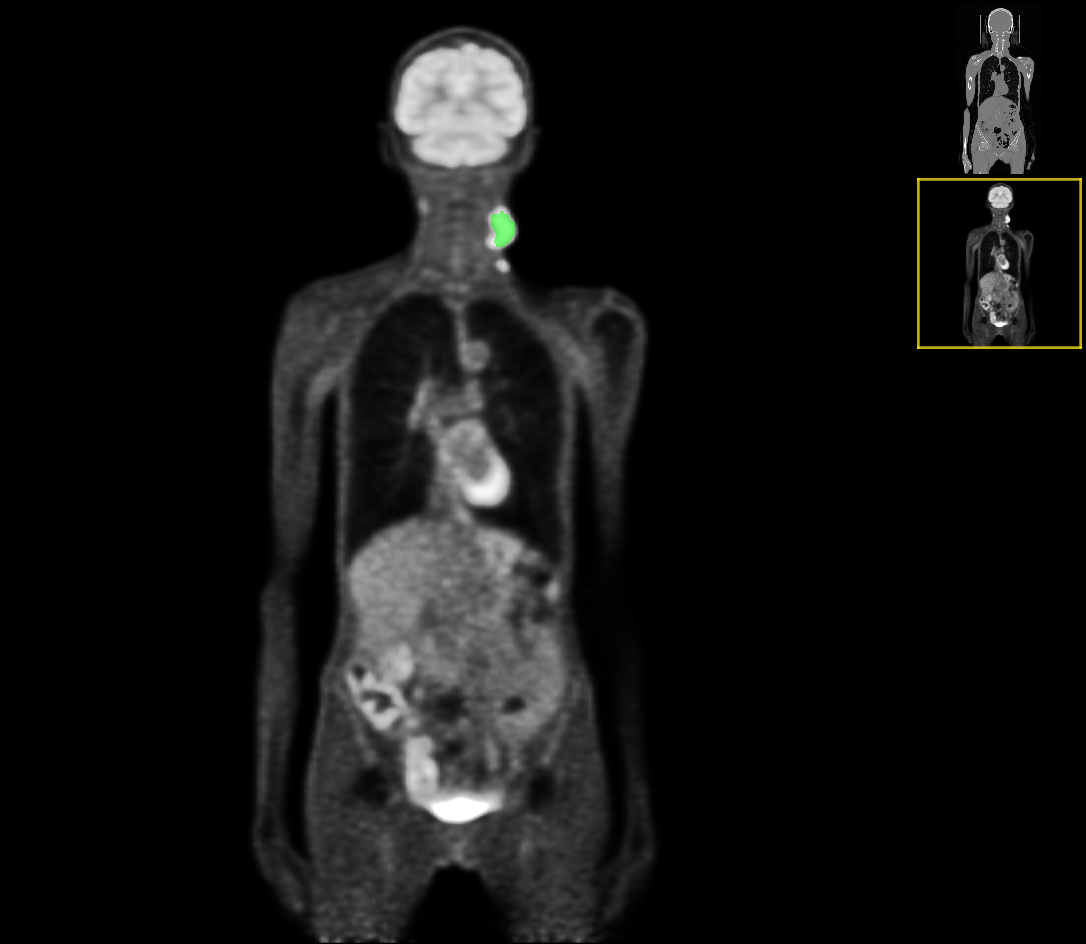

The ground truth labels usually include a single mass of the primary tumor (but in some cases it was absent completely or had two components), and several connected components of the annotated lymph nodes. An example case of CT and the corresponding PET image with ground-truth overlays is shown in Figures 1 and 2.